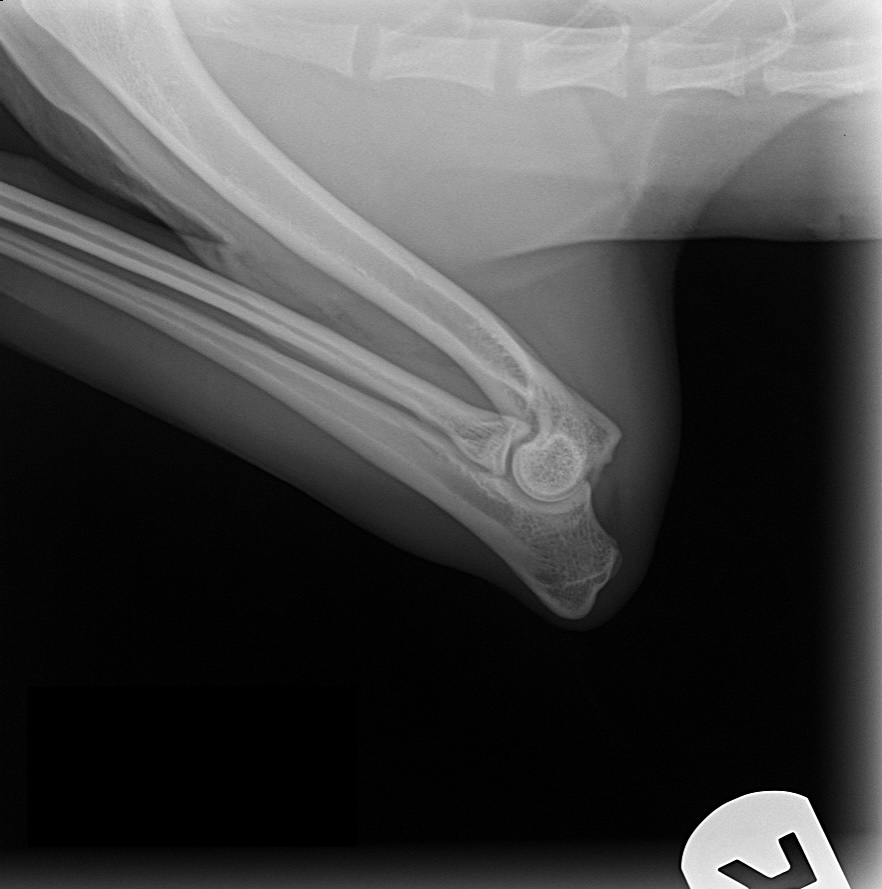

ofa | elbow

rating | normal